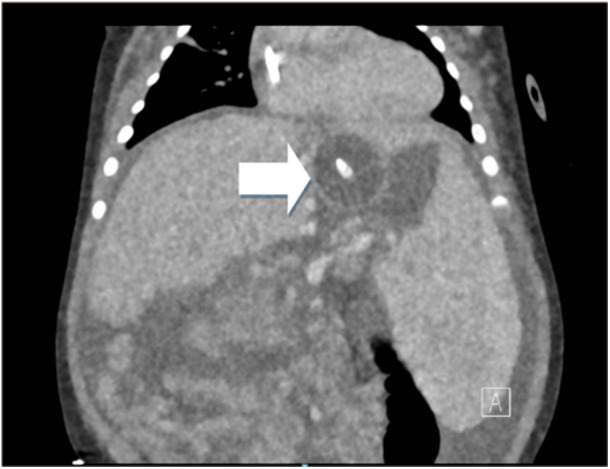

Gastroesophageal variceal bleeding is the most serious complication of portal hypertension. The interventions available including sclerotherapy, variceal banding, and balloon tamponade, are limited by patient age. A 4-month-old with congenital cytomegalovirus, cholestasis, splenomegaly presented to the emergency room after two episodes of hematemesis. The patient required a transfusion of packed red blood cells for anemia. Upper endoscopy revealed no active bleeding, four grade 3 esophageal varices with red wale signs, and a single gastric varix. Sclerotherapy into high-risk varices was completed. Forty-eight hours later, patient developed re-bleeding. Upper endoscopy revealed bright red blood in the stomach. A large clot at the gastroesophageal junction was attributed to the gastric varix. Given the age of the patient and small size, endoscopic bleeding control interventions were limited. A foley catheter was placed in an orogastric manner for balloon tamponade. The intervention was a temporizing measure to allow for transfer to a liver transplant center.